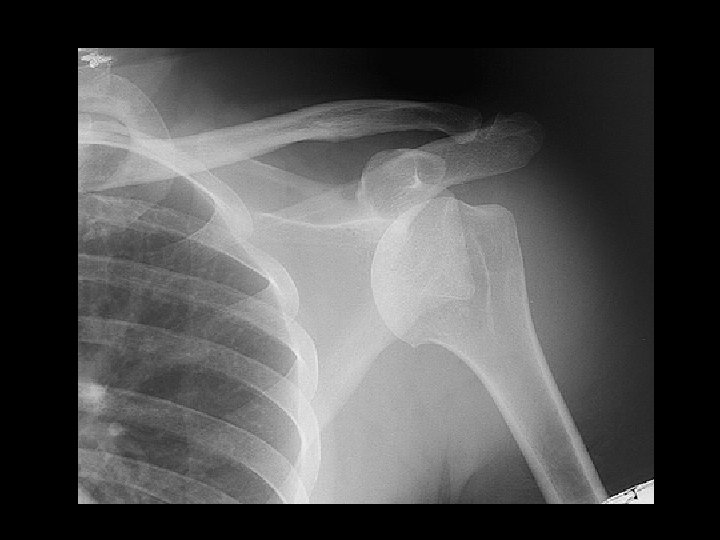

Anterior Shoulder Dislocation

Inferior shoulder dislocation • Findings: – Inferior dislocation of humeral head and a deep cleft in the superior portion • ddx: – Anterior dislocation